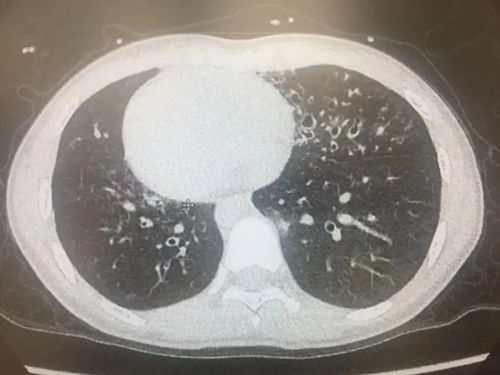

痰是气管、支气管、肺泡的分泌物或渗出物,有粘液、浆液、脓液、纤维蛋白、坏死组织与。

咯痰是呼吸道内的病理性分泌物,借助咳嗽而排出体外的动作。